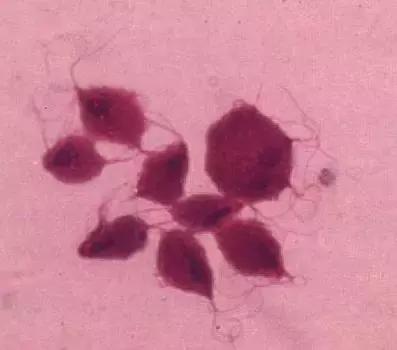

宫颈癌主要是由HPV病毒引起,HPV病毒也叫人类乳头瘤病毒,是一种属于乳多空病毒科的乳头瘤空泡病毒A属,是球形DNA病毒,能引起人体皮肤黏膜的鳞状上皮增殖。

感染者常表现出寻常疣、生殖器疣(尖锐湿疣)等症状。随着性病中尖锐湿疣的发病率急速上升和宫颈癌、肛门癌等的增多,人乳头瘤病毒「 hpv」 也 越来越引起人们的关注。